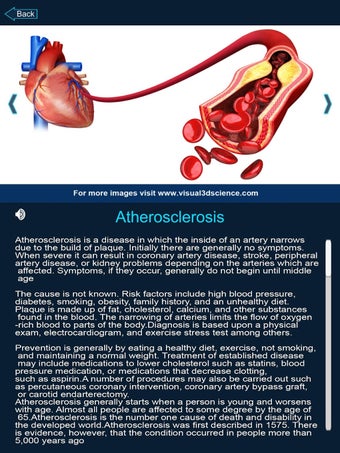

Je kunt alle informatie over de organen krijgen, inclusief hun locatie, hun functie en hoe ze eruitzien.